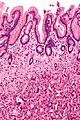

Signet ring cell carcinoma, abbreviated SRCC, is a type of malignant epithelial neoplasm that can arise from a number of places. It is commonly associated with the stomach.

Microscopic

Features:

- Signet ring cells resemble signet rings.

- They contain a large amount of mucin, which pushes the nucleus to the cell periphery.

- The pool of mucin in a signet ring cell mimics the appearance of the finger hole.

- The nucleus mimics the appearance of the face of the ring in profile.

- Signet ring cells are typically 2-3x the size of a lymphocyte.

- Smaller than the typical adipocyte.

- Often have a crescent-shaped or ovoid nucleus.

- Capillaries sectioned on their lumen have endothelial cells - the nuclei of these are more spindled.